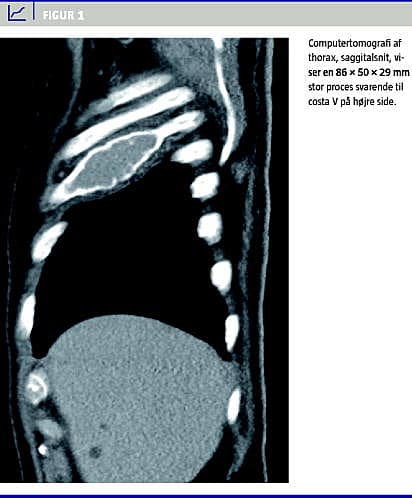

Computertomografi (CT) af thorax viste, svarende til costa fem på højre side, en 86 × 50 × 29 mm stor proces primært med intratorakal ekstension og periostal reaktion (Figur 1 , CT af thorax, sagittal rekonstruktion). Desuden generaliseret, spættet knoglestruktur svarende til hele skelettet. Svarende til Th7 sås patologiske frakturer, samt afrundede opklaringer svarende til Th7, L1 og L3. Der var ingen forstørrede lymfeknuder i mediastinum, aksillerne eller abdomen.